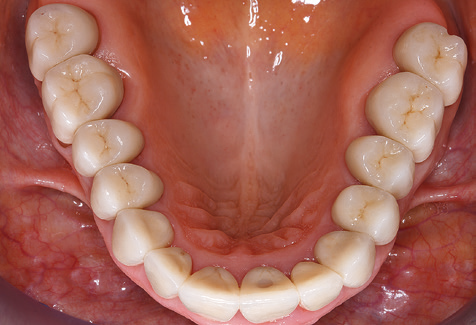

The ten-year check-up revealed no indications of advancing clinical attachment loss or peri-implant bone substance loss (Fig. 3).

Standardised and regular risk-adapted care in the scope of SPT is the key to treatment success for the clinical long-term success in periodontically compromised patients. This is particularly true for patients fitted with implants following successfully completed periodontal treatment (Fig. 11a and b).